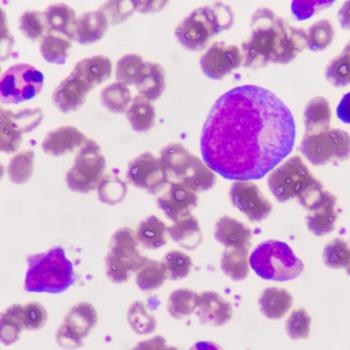

New AQUILA data show PFS improvement in patients with smoldering multiple myeloma who were treated with subcutaneous daratumumab vs active monitoring.